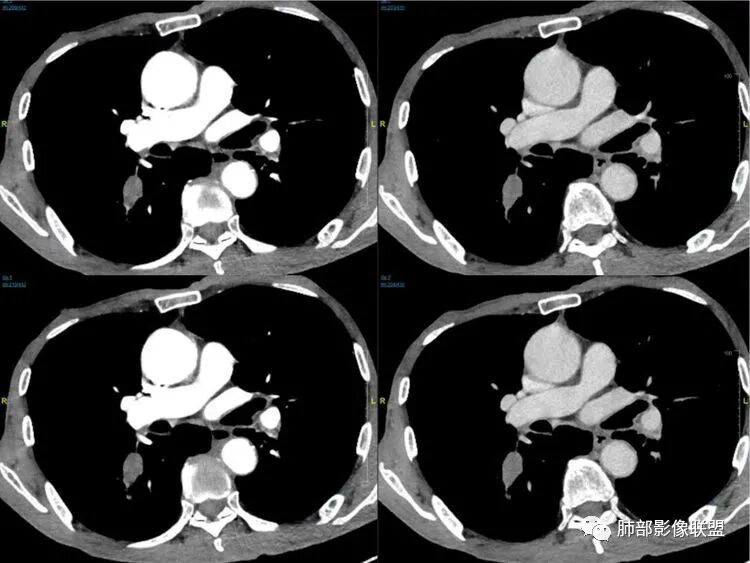

病理结果:小细胞肺癌

关于小细胞肺癌

小细胞肺癌(Small Cell Lung Cancer,SCLC)约占肺癌的15%-30%,起源于支气管粘膜或腺上皮内的Kulchitsky细胞(嗜银细胞),是一种小细胞组成的恶性上皮肿瘤,恶性程度极高、转移早、易复发、预后差、放化疗敏感。

临床特点:发病年龄35-68岁,平均发病年龄60岁,男性多于女性。吸烟为高危因素,早期可无症状,咳嗽为最常见症状,刺激性干咳、咯血、胸闷、气短,进而出现胸痛、上腔静脉综合征、Horner综合征等及各部转移引起相应的症状和体征。

CT主要表现:

1鸭蹼状突起、腊肠样尾巴、指状突起、蠕虫、分支及条状

因为病灶沿支气管粘膜下及周围血管生长,走形方向与支气管一致,所以支气管血管周围生长也是SCLC的典型征象。当然有时会像小山丘或者灌汤包一样趴在肺边缘。

2娘小崽大、淋巴及血行转移早、冰冻纵隔及肺门、血管脂肪间隙消失

因为病灶侵袭力强,病灶易沿淋巴道、间质及心血管间隙等结构侵犯并密切挤压上述结构,常常能够观察到脂肪间隙消失。易于出现冰冻纵隔。原发灶与肺门转移灶可形成哑铃状外观,甚至转移灶体积大于周围原发灶,有人称之为“娘小崽大”。早期病灶有时很小甚或隐匿,仅能看到转移灶,或转移淋巴结与原发灶融合分界不清。病变向肺门延续的串珠样淋巴结转移也是SCLC的典型特点。

3

血管包埋征

病灶侵袭力强大,早期沿粘膜下疏松结缔组织及血管旁间隙扩散,包绕血管,血管会受压变形,因为小细胞癌破坏力弱,血管没有被破坏,所以仅仅表现为包埋浸润,但血流面光滑。

4

乏血供,沼泽样坏死

、罕见空洞

病灶肿瘤密集而供血血管相对不多,密度较均匀,轻度强化,呈乏血供,有时候可以坏死,坏死不彻底,坏死区分散而较小,呈沼泽样坏死,很难造成引流支气管的破坏,所以空洞罕见。

5

阻塞性炎症轻,阻塞性肺不张少见

支气管内肿瘤大多来自淋巴结转移,而且侵入支气管管壁的SCLC组织喜欢沿粘膜下组织间隙浸润,支气管粘膜面保留,所以支气管大多数表现为狭长而非填塞或截断,所以阻塞性炎症轻,阻塞性肺不张罕见。

6边缘圆钝、光整,未见毛刺

神经内分泌肿瘤边缘通常圆钝,而且SCLC或周围没有任何促纤维结缔组织反应,质地软,所以边缘圆钝、没有毛刺。